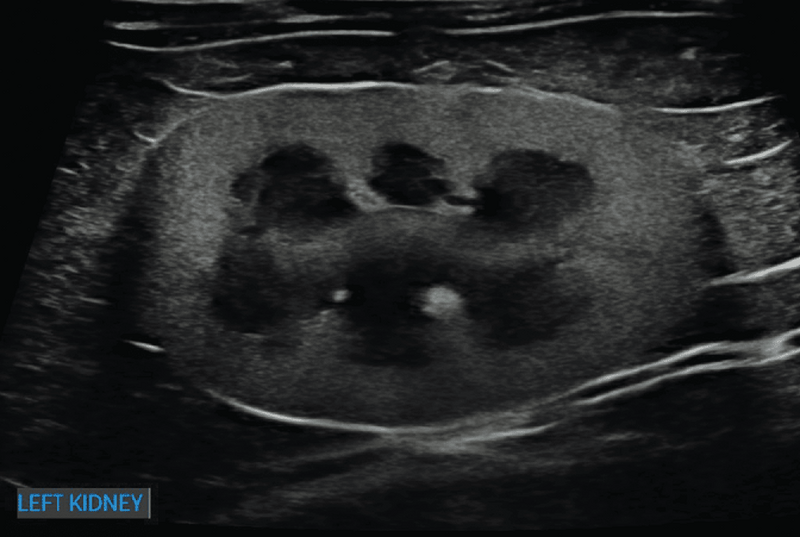

Prawidłowy obraz ultrasonograficzny nerek został szczegółowo omówiony w innych źródłach,7 a poniższy artykuł koncentruje się na przewlekłej chorobie nerek u kotów i psów. Nerki powinny być obrazowane w trzech projekcjach – strzałkowej, dogrzbietowej i poprzecznej (ryc. 1).7 U psów, zwłaszcza małych ras, opisano obecność hiperechogenicznego zewnętrznego pasma rdzeniowego, które obserwuje się z umiarkowaną częstością u pacjentów bez stwierdzonej choroby nerek (ryc. 2).8 U kotów kora nerek może być jednorodnie silnie hiperechogeniczna ze zwiększonym w następstwie zróżnicowaniem korowo-rdzeniowym wtórnym do lipidozy kanalików bliższych (ryc. 3).9 Odkładanie się tłuszczu w kanalikach nerkowych jest konsekwencją otyłości bez jednoczesnego upośledzenia czynności nerek.10 Dodatkowo rutynowo obserwuje się zależny od kąta badania artefaktowy wzrost hiperechogeniczności kory i rdzenia nerek, wtórny do anizotropii, w obszarach, w których kanaliki nerkowe ułożone są prostopadle do płaszczyzny fali ultradźwiękowej. Na przykład podczas obrazowania nerki w projekcji strzałkowej echogeniczność biegunów doczaszkowego i doogonowego będzie ogniskowo i artefaktowo zwiększona (ryc. 4).11 Z doświadczenia autorów wynika, że łagodna nieregularność brzegów nerek, szczególnie u kotów, może być obserwowana w miejscach, gdzie naczynia nerkowe przebiegają wzdłuż torebki nerkowej, i nie powinna być błędnie interpretowana jako zmiana zwyrodnieniowa (ryc. 5). W lokalizowaniu tych naczyń użyteczna jest ultrasonografia dopplerowska kodowana kolorem lub w trybie mocy.

Ryc. 3. Obraz w projekcji strzałkowej lewej nerki kota, przedstawiający wyraźnie zwiększoną echogeniczność kory nerkowej, skutkującą wzmożonym zróżnicowaniem korowo-rdzeniowym, co jest najbardziej zgodne z rozpoznaniem lipidozy kanalikowej. To zjawisko u kotów często powoduje, że nerki są hiperechogeniczne w stosunku do wątroby i/lub śledziony.